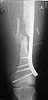

We fluoroscoped every thing in the OR under anesthesia. It was clear that the Ltproximal side is unstable, in mal-position and the nail is probably outproximally.

On the Rt side, the proximal construct was stable but the distal (the shaft fx)was not.

AP Pelvis

Lt femur

Rt femur

Lt hip

Rt hip

Lt leg incisions

We decided to fix the Lt femur with a few lag screws on the proximal part andstabilize the femur with long Richard plate that was inserted in a sub-muscularfashion, in order to avoid opening the main shaft fx (the so-called biologicfixation - see Lt leg incisions.).

On the Rt side I replaced the recon nail with a longer one (accepting its toolateral and anterior entering point), I added a proximal locking screw (anterior toposterior) in the subtrochanteric region through a self-made extra hole, and two 6.5cancellous hip screws posterior to the nail.